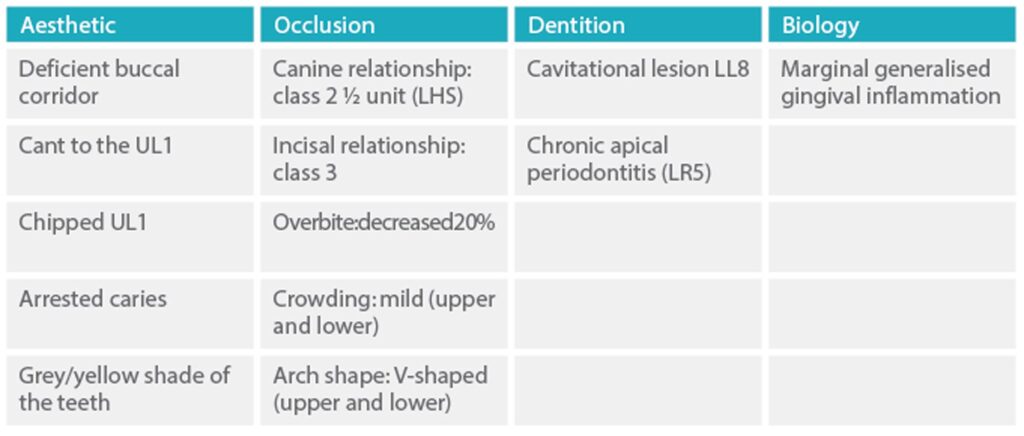

The results of the extraoral and intraoral examinations are summarised in a problem list (Table 1). Based on this list, an interdisciplinary approach helped to define all the potential treatment goals.

Table 1: Problem list